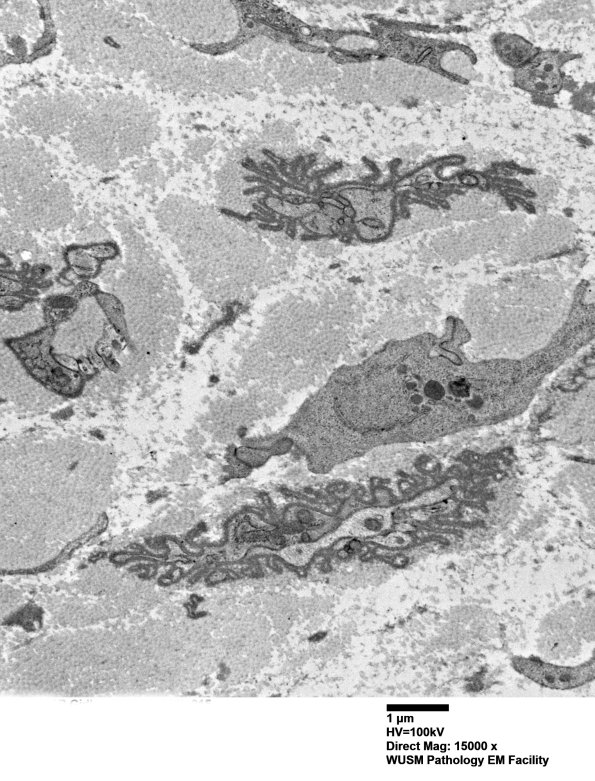

6B4-6 There is nearly complete loss of axons with corrugated collapsed basal lamina covering a few small residual Schwann cell processes. The matrix is composed of collagen with admixed oxytalan. (electron micrographs)